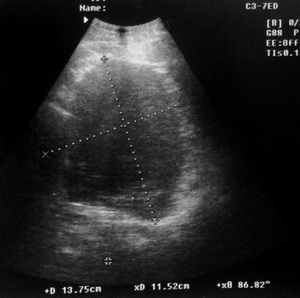

Но.... был у нас тут недавно случай: мужчина 58л, жалобы на боли в левом подреберье, из анамнеза Рак p.Fateri T2N0M0 IIст, IIIкл.гр., после ПДР.

Из протокола УЗИ: в воротах селезенки виз-ся жидкостное образование разм.... инкапсулированное, неоднородной структуры с вероятными признаками абсцедирования.Закл: По УЗ-признакам нельзя исключить абсцесс в воротах селезенки.

19062012649.jpg

19062012649.jpg (45.63 КБ) 1226 просмотров

19062012656_cr.jpg

19062012656_cr.jpg (44.96 КБ) 1226 просмотров

Операция: Абсцесс селезенки...

Поэтому и в представленном С.В. случае можно предположить абсцесс :?